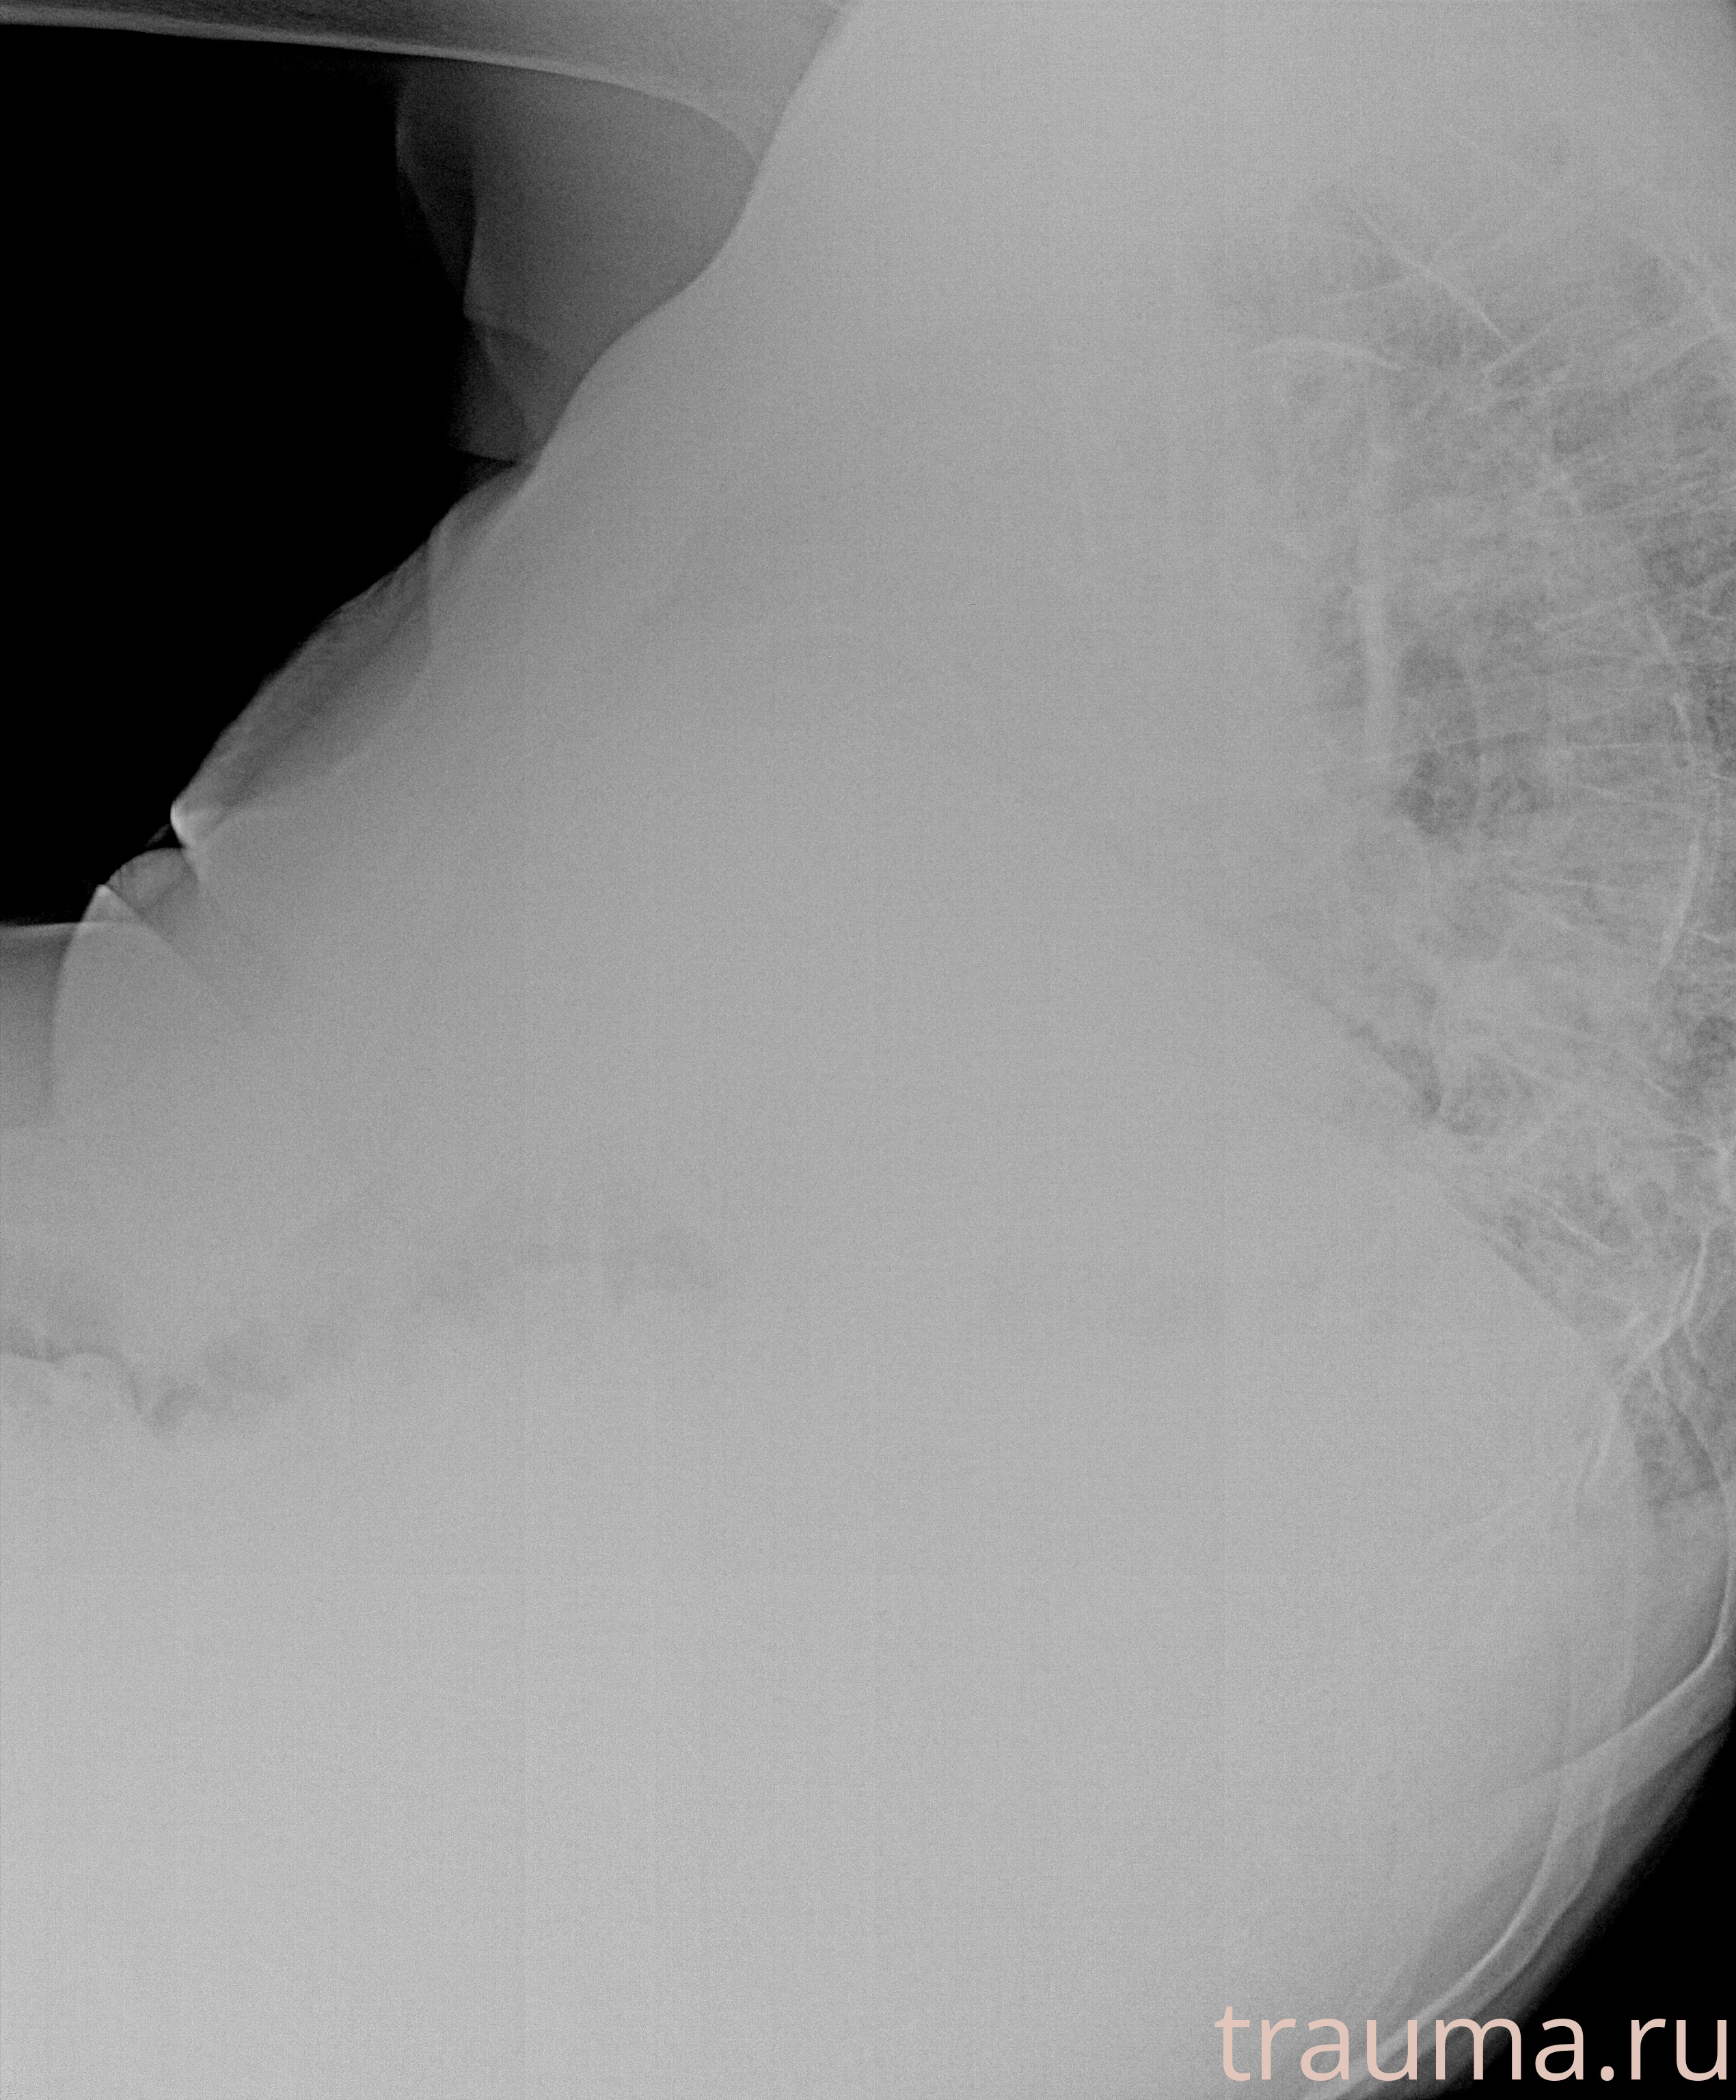

Рентгенограммы

Рентген на дому: по вашему адресу приезжает врач-рентгенолог, травматолог-ортопед с мобильным рентгеновским аппаратом, проводит диагностику травмы или заболевания, делает необходимые рентгенограммы, дает рекомендации по дальнейшему лечению. Получить качественные снимки в домашних условиях возможно благодаря уникальной методике, разработанной МосРентген Центром для института  Склифосовского